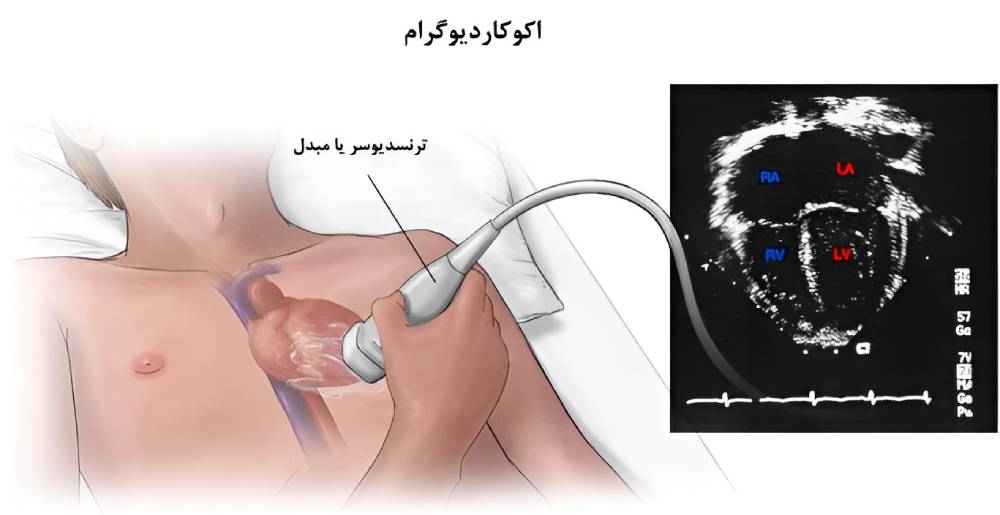

اکوکاردیوگرام

اکوکاردیوگرافی نوعی اسکن است که در آن از امواج صوتی برای تهیۀ تصویر از داخل قلب استفاده میشود. اکوکاردیوگرافی در اصل سونوگرافی قلب است. اکوی قلب برای شناسایی دقیق بخشهای آسیبدیدۀ قلب و تأثیر این آسیبدیدگی بر عملکرد قلب مفید است.